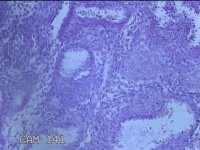

宫腔内容物

性别

女

年龄

39岁

临床诊断

1.子宫内膜息肉 2.中度贫血

一般病史

不规则阴道流血24天。

标本名称

大体所见

灰白暗红色不规则碎组织2.5x2.3x0.7cm一堆。